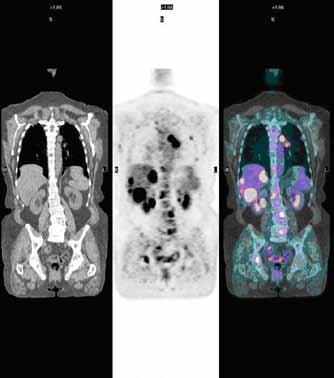

35 Introduction to Nuclear Medicine by Dr. Bennett S. Greenspan

Dr. Ben Greenspan, M.D. (U.S.), Board of Directors, the American Board of Science in Nuclear Medicine; Past President, Society of Nuclear Medicine and Molecular Imaging